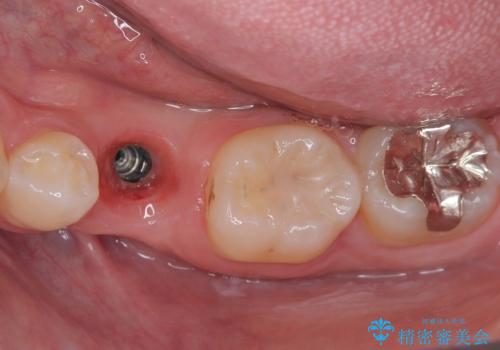

永久歯の先天欠如 インプラントによる補綴

- 乳歯を抜歯したところにインプラントをしたいと来院された患者様です。

永久歯の先天欠如による乳歯の晩期残存があり、その乳歯が虫歯になってしまい保存不可能になり、他院で抜歯をし義歯を使用していた状態です。

義歯では嚙みづらいため、インプラントによる補綴をしていくこととしました。

なお、反対側も永久歯先天欠如による、乳歯の残存がありますが、特に齲蝕も認められないため処置をせず、できるだけ保存していくこととしました。

義歯と違ってしっかり噛めるようになって食事がおいしくなったと満足していただけました。